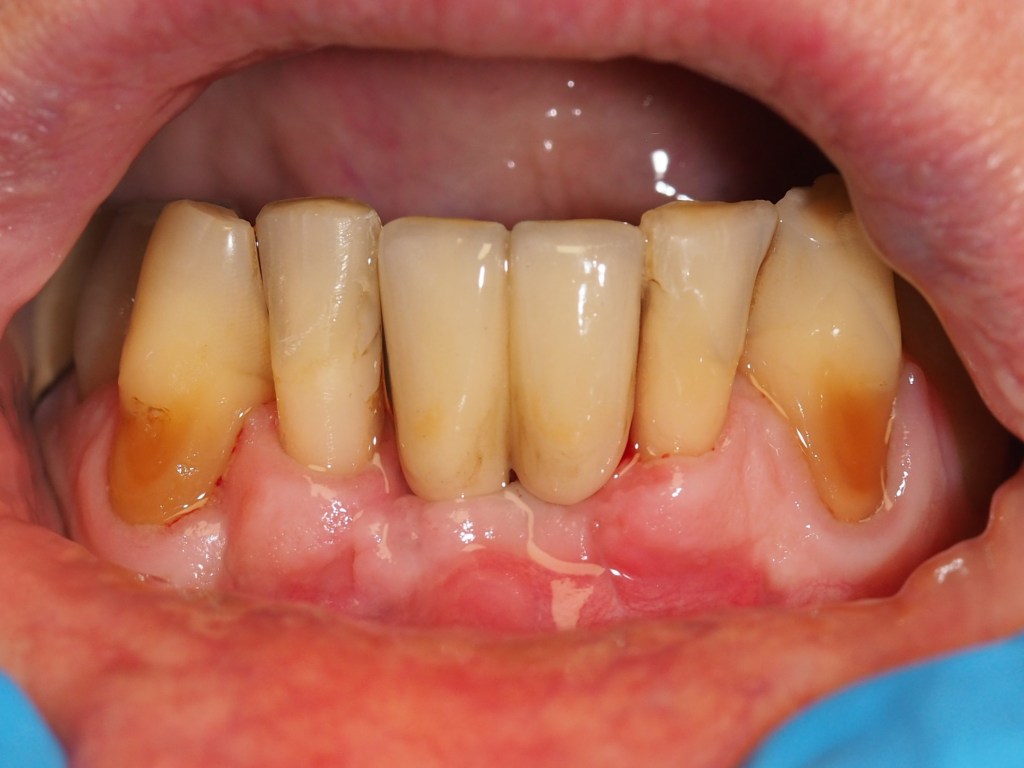

Después de una minuciosa primera visita y el estudio de las pruebas complementarias vemos que hay desgastes por ácidos que han llevado a una disminución de la dimensión vertical de oclusión (DVO), que a su vez han desencadenado en una inestabilidad oclusal y a un aumento de la actividad muscular (bruxismo). Además, presenta apiñamiento en los incisivos inferiores y dientes superiores “cortos” debido a una erupción pasiva alterada (EPA). (Figuras 1-6)